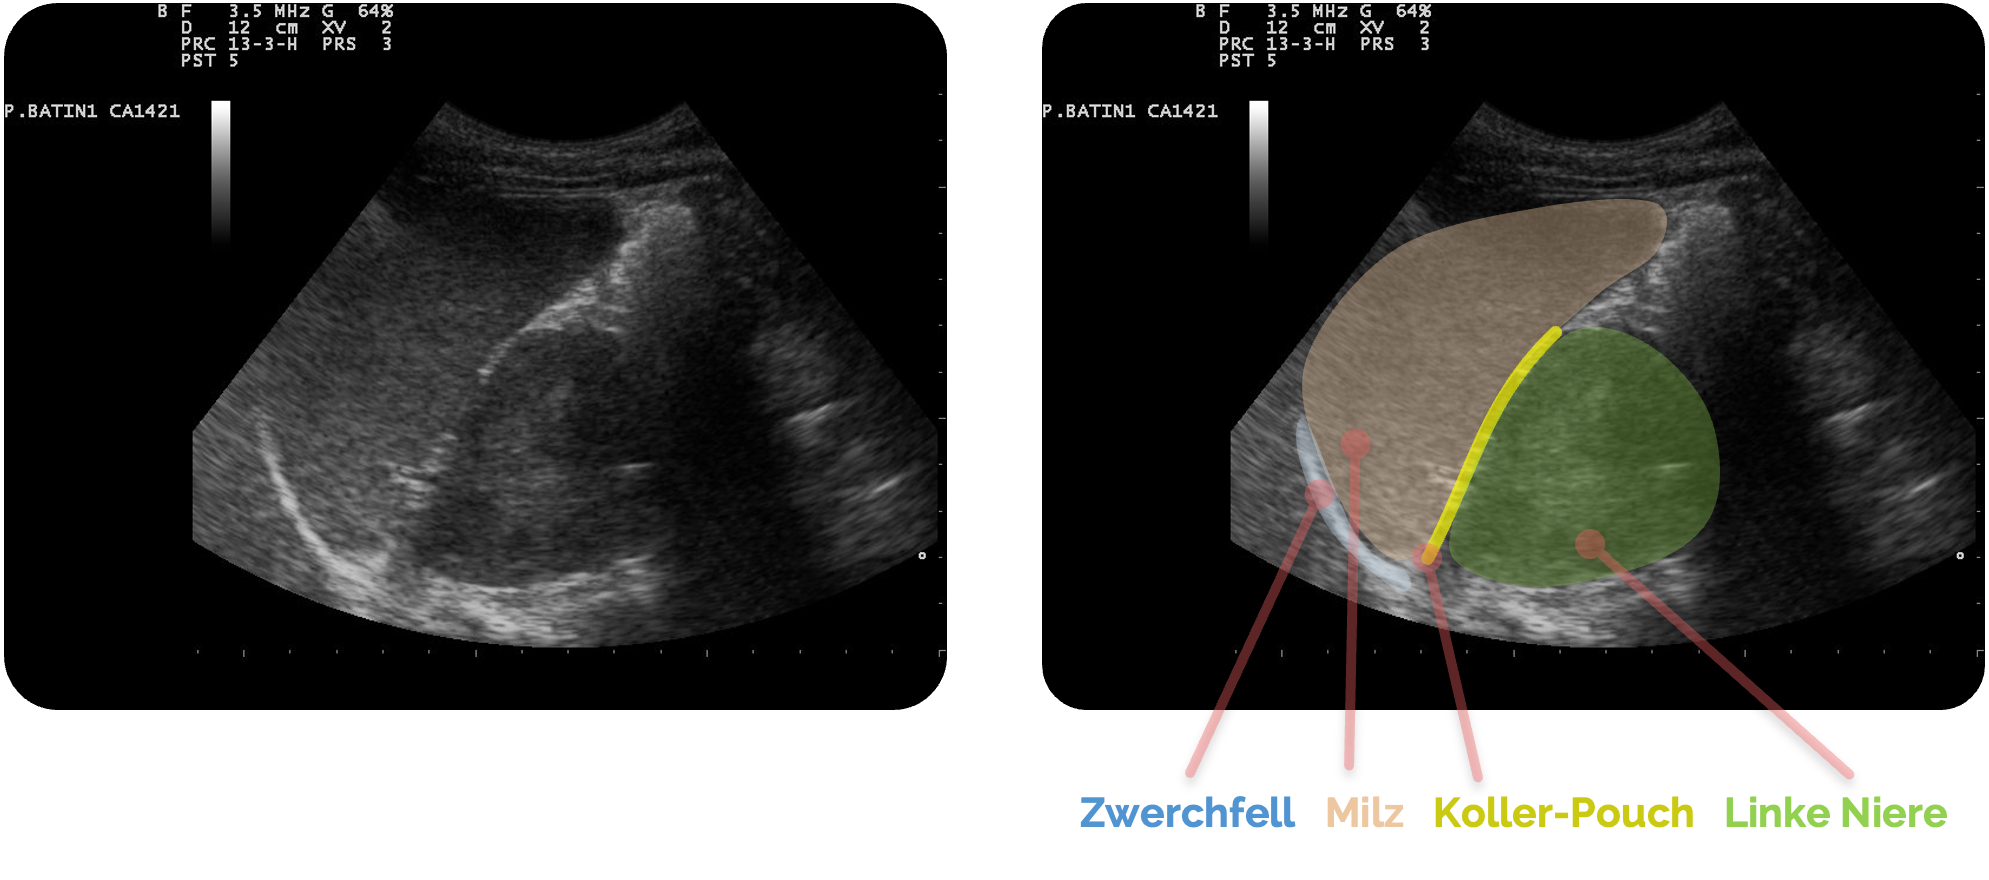

Normalbefund

Im Normalbefund zeigt sich der Koller-Pouch als enger Kontaktbereich zwischen Milz und linker Niere, ohne erkennbare Flüssigkeitssichel zwischen beiden Organen.

Die Milz erscheint homogen echoreich, das Nierenparenchym echoarm mit zentralem Echokomplex. Die Grenzflächen sind glatt und klar voneinander abgrenzbar. Zwischen Milz und Niere darf sich keine echofreie Zone befinden. Selbst ein schmaler Flüssigkeitssaum ist bereits pathologisch.

Bei tiefem Atemzug kann die Milz leicht über den oberen Nierenpol gleiten, was ein Zeichen normaler Organbeweglichkeit ist. Auch unter Veränderung der Schallebene (Längs- oder Schrägschnitt) bleibt der Raum frei von Flüssigkeit und die Konturen der Milz bleiben gleichmäßig definiert.

Ultrasound image of spleen 110318090022 0905570.jpg, Nevit Dilmen, CC BY-SA 3.0, https://creativecommons.org/licenses/by-sa/3.0, via Wikimedia Commons. Es wurden die Markierungen und Beschriftungen ergänzt.

Anatomische Varianten sind häufig: Die Milz kann unterschiedlich groß oder leicht rotiert liegen und der obere Pol der linken Niere ist teils durch die Colonflexur oder den Magen

Auch die Zwerchfelllage variiert je nach Atemphase und Körperposition. In manchen Fällen lässt sich der Recessus splenorenalis nur durch leicht schräges Kippen der Sonde oder Änderung des Patient:innenwinkels vollständig darstellen.